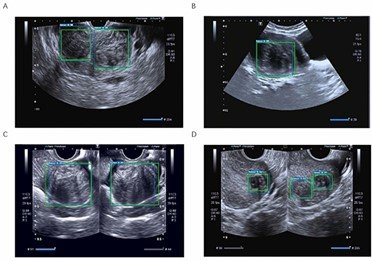

-سونوگرافی لگن: روشی که طی آن یک ابزار کوچک به نام مبدل یا داخل واژن قرار داده می شود یا از روی شکم با استفاده از امواج صوتی تصاویری از اندام های داخلی ایجاد میکند که پزشک می تواند اندازه، شکل و بافت رحم را ببیند و هرگونه رشد را ارزیابی کند.